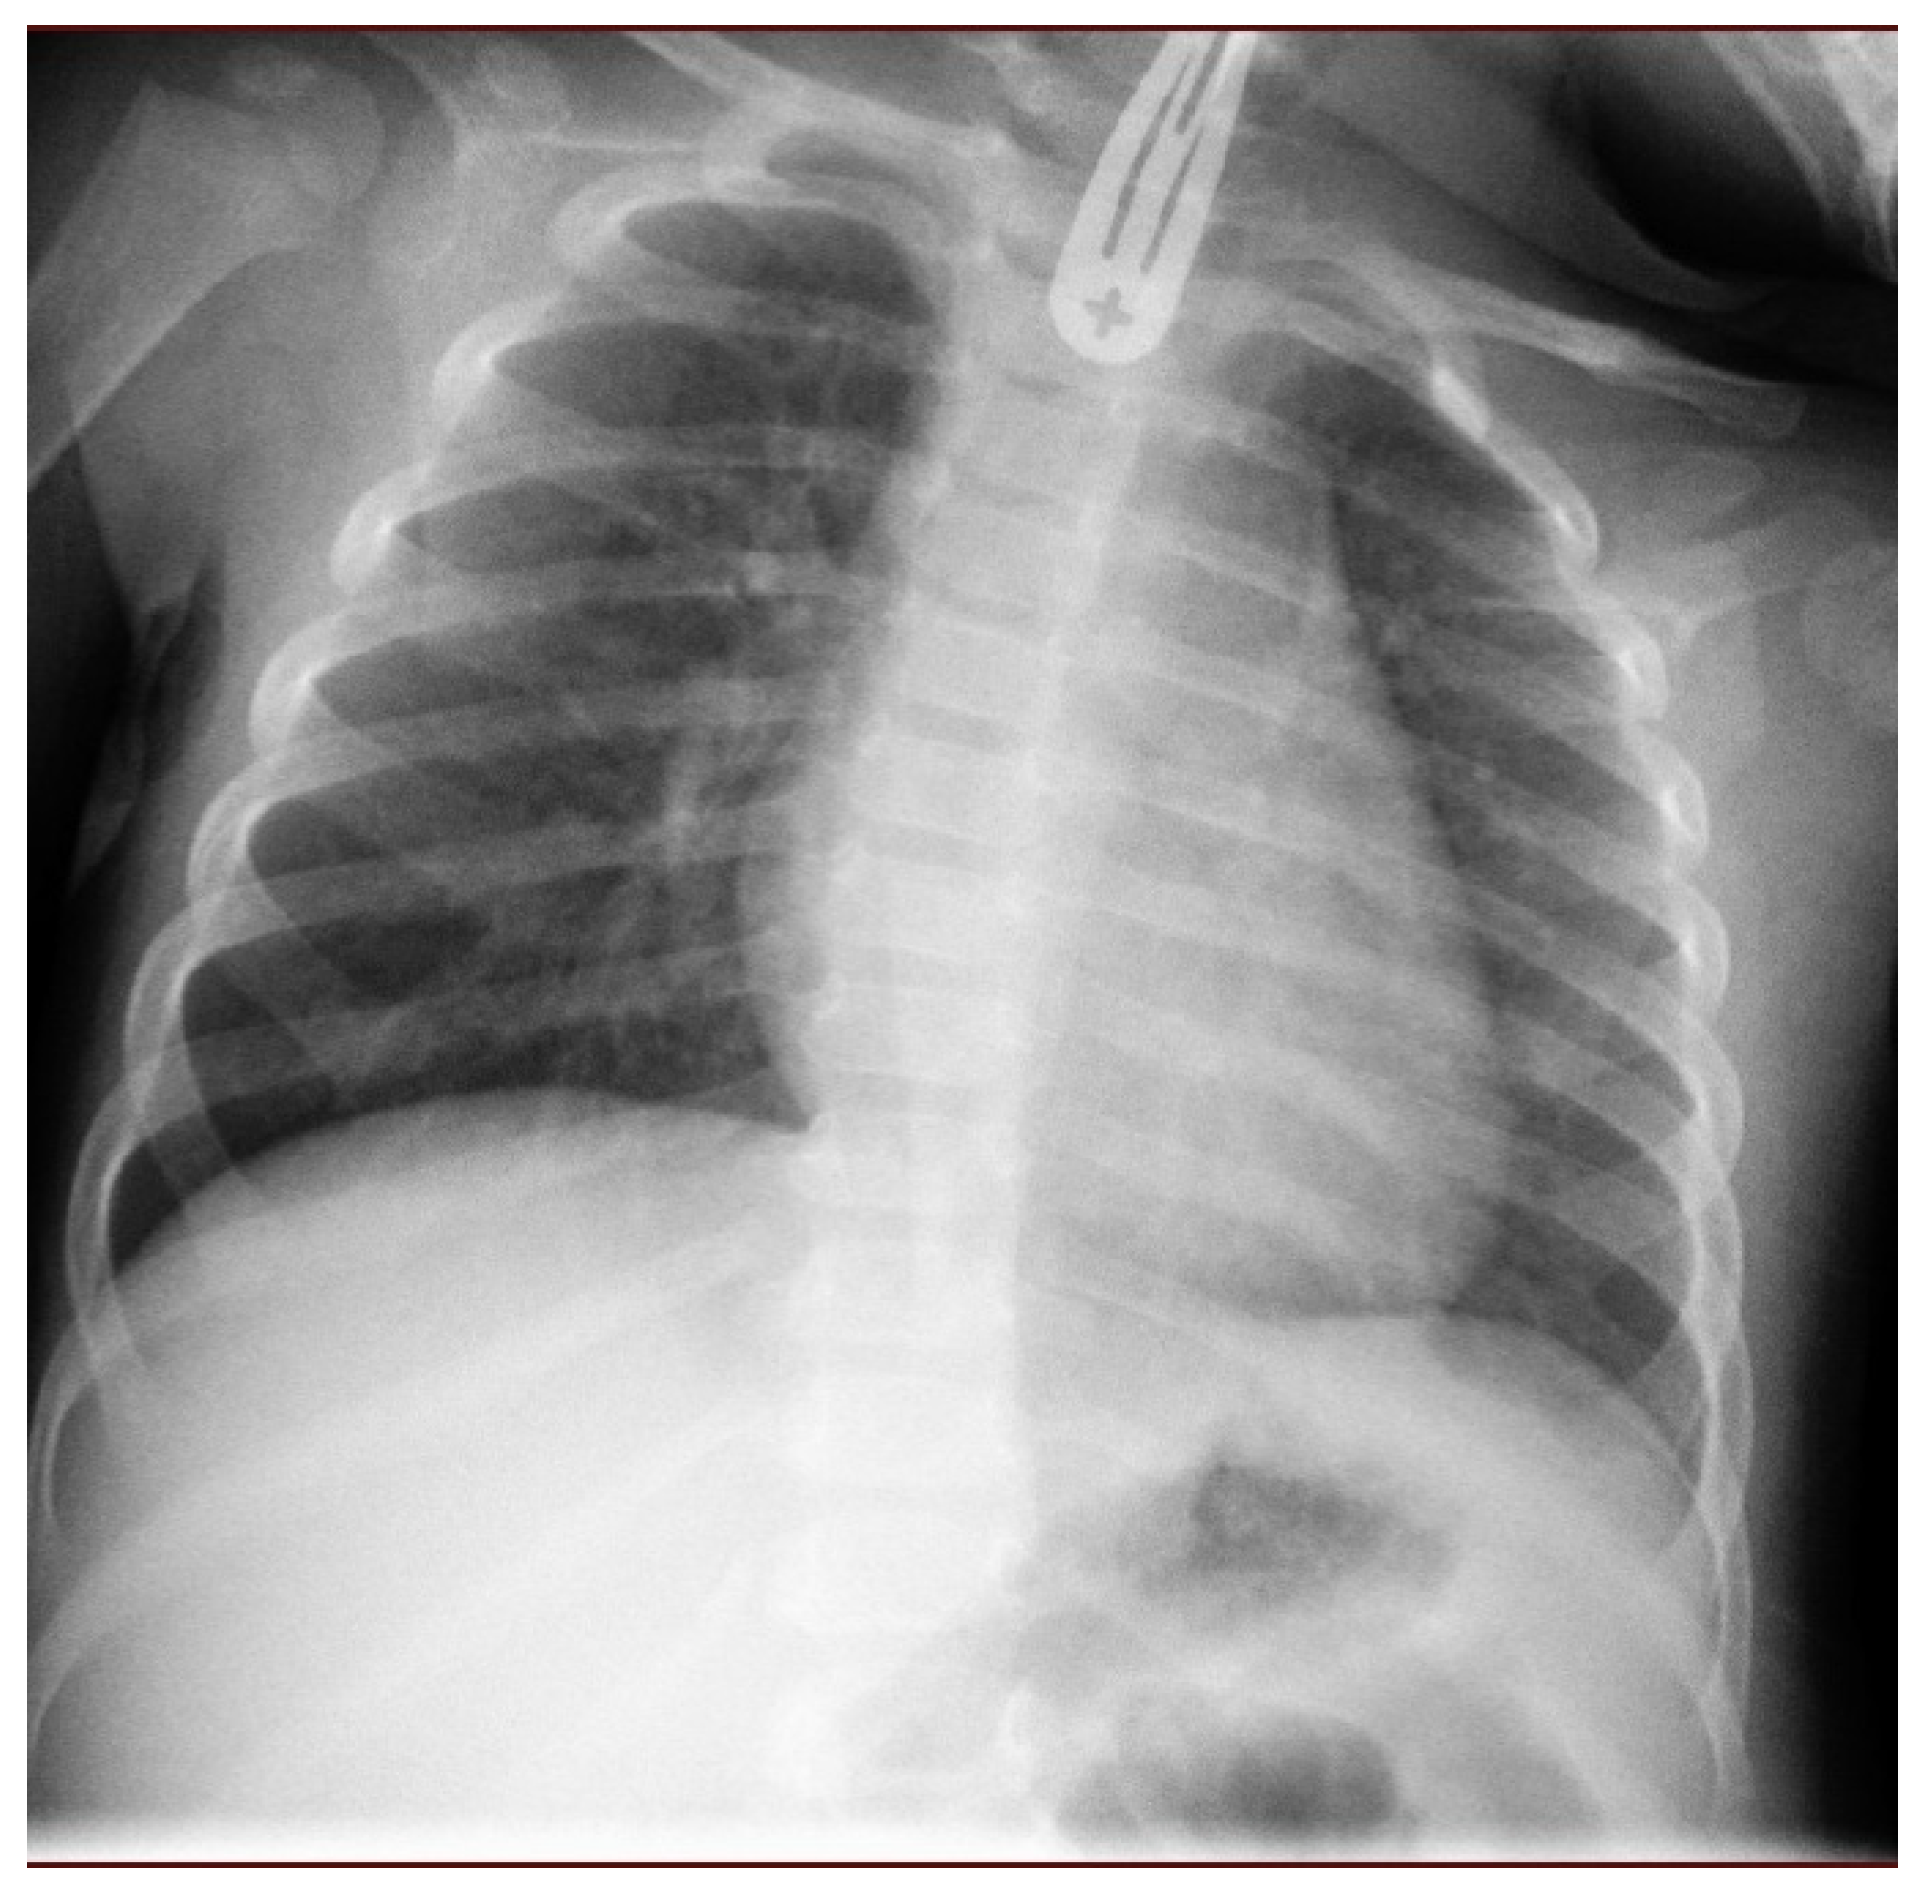

- Quick admission, processing, and basic tests, such as blood tests and chest X-ray;